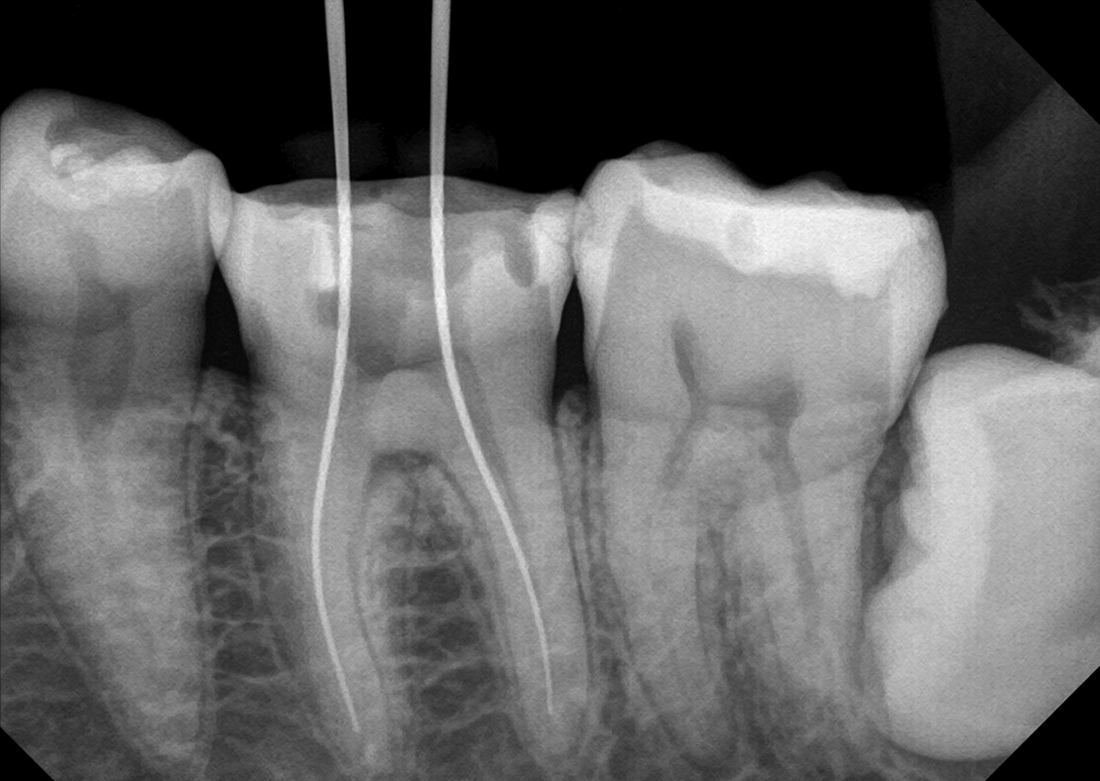

KLIMIKAI FELVÉTELEK

Hosszú tapasztalat során felhalmozott szakértelmünkkel kiváló diagnosztikai képeket biztosítunk.

Ez a Genoray büszkesége, amelyet világszerte szeretnek.